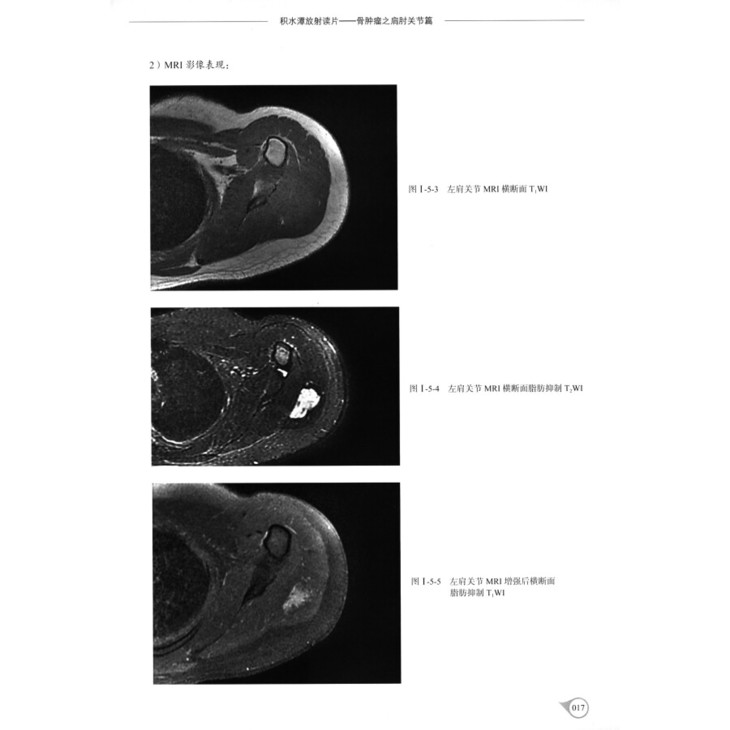

病例5